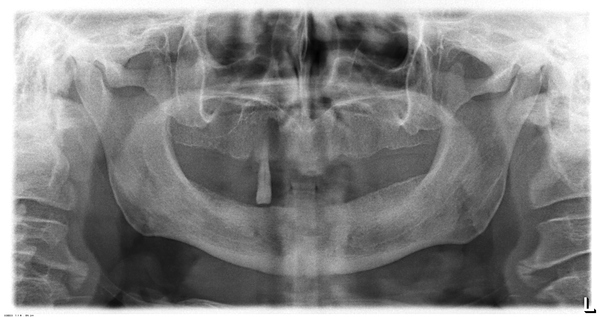

На обзорной рентгенограмме (ОПГ или ОПТГ - ортопантомограмма) это выглядит вот так:

К случаям как на последней картинке мы ещё неоднократно вернемся, а пока давайте рассмотрим такое явление как кариес.